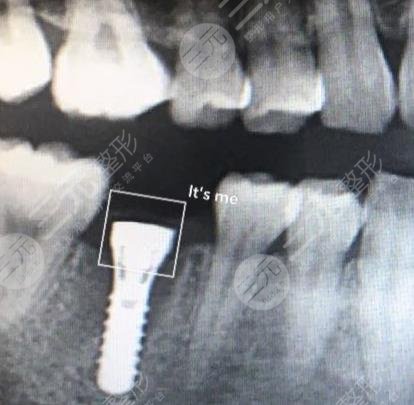

手术项目:种植牙

在治疗的过程中,医生决定把虫牙和一些扭曲的牙齿拔除,然后采用种植牙手术的技巧,来让自己的空缺部位得到填充,从而让整个口腔看上去更加的协调和工整,经过一系列的医学讨论之后达成了共识,较终开展了种植牙手术。手术结束之后,医生让我吃了一些消炎药和活血化瘀的药物,也让我好好的休息,尽量不要吃辛辣和油腻的食物,所以每天喝了很多的温开水,也吃了很多新鲜蔬菜和水果,整个口腔恢复的特别的好,种植牙手术之后的牙龈,也没出现疼痛的感觉。